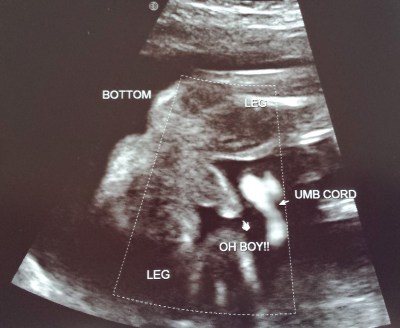

Ultrasound #3

On May 13th, we went in for the big halfway appointment. It was at this appointment that we’d learn a lot more about how our baby was growing. Did everything look normal? Was there anything weird or suspicious or scary? We also hadn’t seen any pictures of him for a long time (11 weeks), and we were going to be able to learn the baby’s sex, so it goes without saying that we were pretty keyed up for this visit.

Since we ultimately learned that everything looked good and healthy and normal, I won’t keep you in suspense about that. The appointment was a lot of fun; the baby was incredibly active- so much so that Matt asked if babies can ever be too active- and had developed so much since we’d last seen it that we were both just totally overcome. Suddenly we were both so much more aware of all of the life that was actually, really growing inside of me.

![]() |

| Look at that profile! Baby has Matt’s nose. |

| This is how we know Baby Nolsen is a runner: those beautiful, strong legs. |